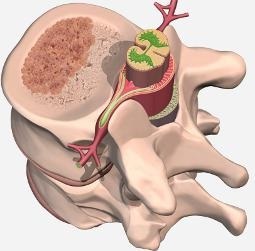

Prin ea insasi, tumora creste lent și nu formează metastaze. Caracteristica principală de localizare - cavitatea corpului vertebral, precum și substanța cartilaginoasă între ele. Cu toate acestea, există alte locuri, mai rare și neobișnuite în oase. În materie de maduva spinarii sunt, de asemenea, de multe ori identificat divizarea celulelor de date vasculare patologice, care confirmă originea locală a educației în creștere.

Pe vertebra deja modificate după naștere de-a lungul vieții lor va oferi o varietate de efecte mecanice și fizice care pot contribui la apariția microtrauma constantă și hemoragie a vaselor de sânge subțiri și fragile morfopatologic. Pentru a opri reacțiile de coagulare activat hemoragie organism, inclusiv formarea unei cantități masive de cheaguri de sânge la nivel local. La celulele același timp activate, osteoclastelor, care distrug osul grinzi corpurile vertebrale și promovarea creșterii de noi vase pe locul gol după procesul de recanalizarea de cheaguri de fibrină de sânge. Deci, încet, dar sigur, există o creștere a conglomerat vasculare patologice.

Având în vedere caracteristica a tumorilor plasa nu este greu de imaginat ce a declanșat principalele simptome ale bolii. Aceasta se manifestă pe fundalul dinamicii locale sub forma unei schimbări negative în parametrul corp pathologically format vertebră înălțimea sa cu dezvoltarea și prăbușirea posibilă comprimarea rădăcinilor nervoase adiacente ce se extind sub formă, cum ar fi hemangioame spinării. Dimensiunea tumorii, mai ales în cazul în care este nevoie de o cavitate vertebrală complet, afectează în mod direct clinica si gradul de manifestare a durerii.